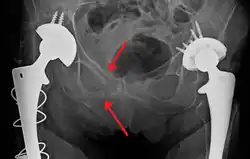

The most common causes of blunt pelvic trauma are motor vehicle crashes and multiple-story falls, and thus pelvic injuries are commonly associated with additional traumatic injuries in other locations.[27] In the pelvis specifically, the structures at risk include the pelvic bones, the proximal femur, major blood vessels such as the iliac arteries, the urinary tract, reproductive organs, and the rectum.[28][27]

.png)

One of the primary concerns is the risk of pelvic fracture, which itself is associated with a myriad of complications including bleeding, damage to the urethra and bladder, and nerve damage.[29] If pelvic trauma is suspected, emergency medical services personnel may place a pelvic binder on patients to stabilize the patient's pelvis and prevent further damage to these structures while patients are transported to a hospital. During the evaluation of trauma patients in an emergency department, the stability of the pelvis is typically assessed by the healthcare provider to determine whether a fracture may have occurred. Providers may then decide to order imaging such as an X-ray or CT scan to detect fractures; however, if there is concern for life-threatening bleeding, patients should receive an X-ray of the pelvis.[30] Following initial treatment of the patient, fractures may need to be treated surgically if significant, while some minor fractures may heal without requiring surgery.[27]

A life-threatening concern is hemorrhage, which may result from damage to the aorta, iliac arteries, or veins in the pelvis. The majority of bleeding due to pelvic trauma is due to injury to the veins.[29] Fluid (often blood) may be detected in the pelvis via ultrasound during the FAST scan that is often performed following traumatic injuries. Should a patient appear hemodynamically unstable in the absence of obvious blood on the FAST scan, there may be concern for bleeding into the retroperitoneal space, known as retroperitoneal hematoma. Stopping the bleeding may require endovascular intervention or surgery, depending on the location and severity.[28]